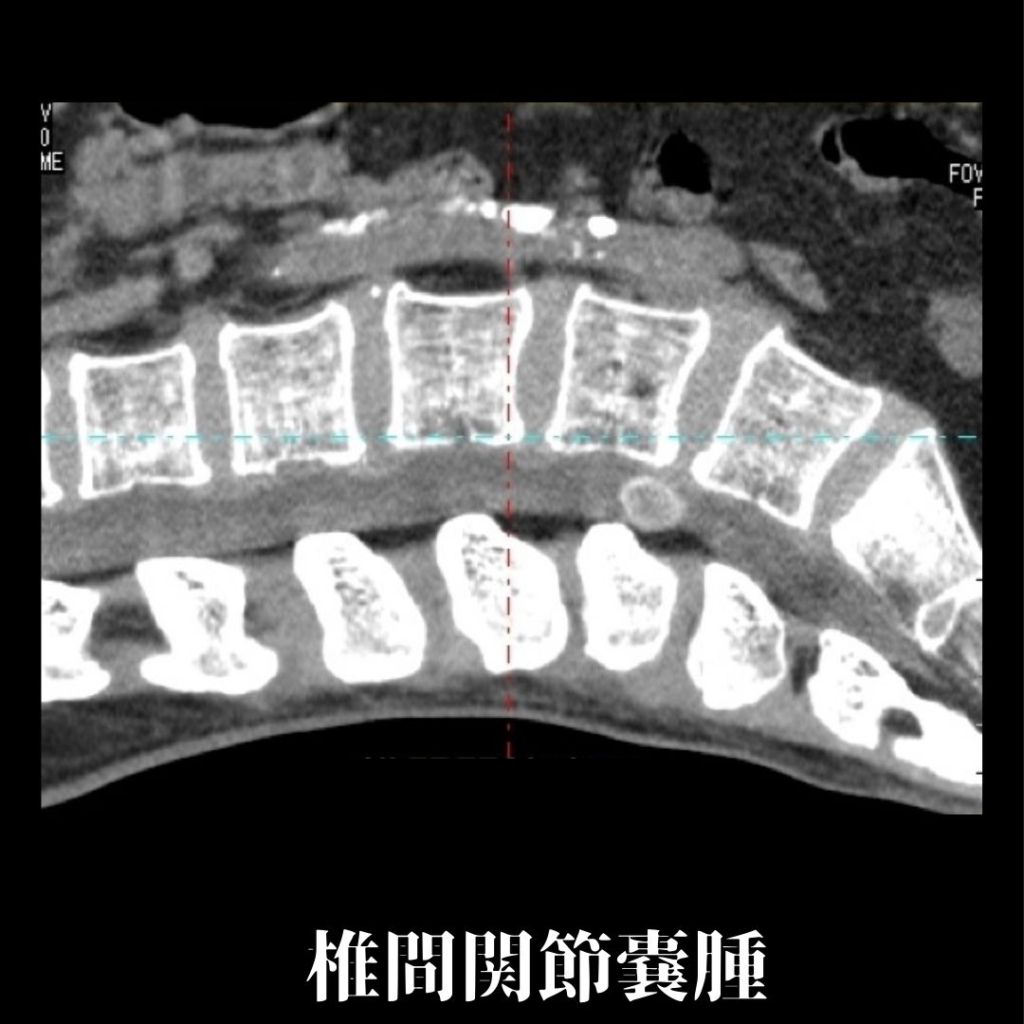

16列マルチスライスCTを完備

当院では、16列マルチスライスCTを完備しております。CTとは、Computed Tomographyの略で、X線を使って身体の断面を撮影することが可能な検査となります。短時間での検査ができ、多くの情報を得ることができます。

脳疾患(脳梗塞、脳出血ほか)、胸部疾患(肺気腫、気胸、肺腫瘍、肺がんほか)、腹部疾患(胃がん、大腸がん、すい臓がん、肝臓がんほか)、骨折等の整形外患ほか、多岐にわたる検査が可能です。